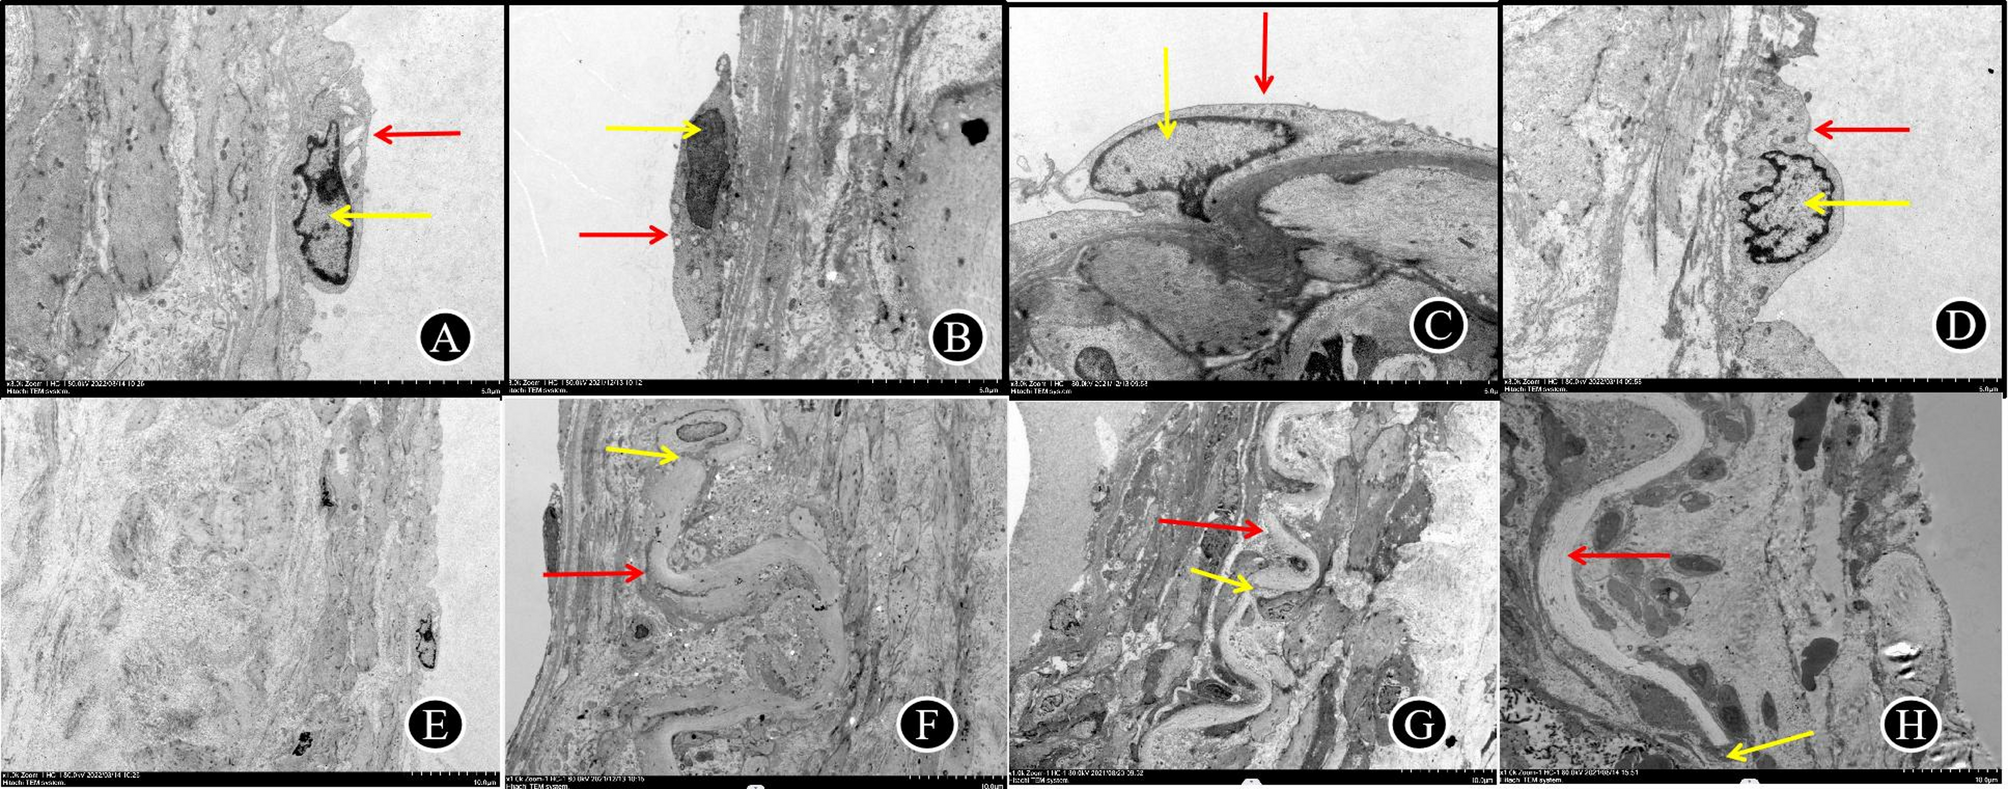

Fig. 5

A–D vascular endothelial cells of hemorrhagic MMD (red arrow) are long spindle shape, complete cell membrane, irregular nucleus (yellow arrow), heterochromatin border.With the Suzuki stage, endothelial cells became pyknosis and necrosis increased; E–H the internal elastic lamina (red arrow) in hemorrhagic MMD was wavy, and the thinning and fracture (yellow arrow) worsened with the progression of Suzuki stage.(A and E:Suzuki II stage; B and F:Suzuki III stage; C and G:Suzuki IV stage; D and H: Suzuki V stage ).